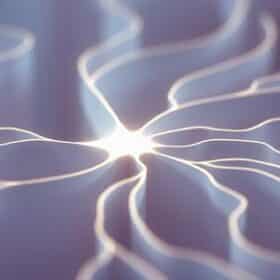

Érinacines: Approhes et Perspectives Dans the neuroprotection Them Érinacines Sont des Bioactifs compositions Dérivés du Champignon Hericium Erinaceus, Également Connu...

Ergothionéine: The Biomolecule Antioxydante Naturelle Dont Tout Le Monde Parle The L-erthionéine begins déjà à être consider Longévité...